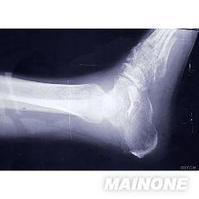

其他较少受累的关节包括:踝关节、足和上肢关节。病人可能有跛行,关节会出现皮温增高、肿胀及活动范围减小。关节结核会严重影响关节功能,即使经过积极正确的治疗,病变也会在某一孤立的部位复发。周围小关节的结核有时会与其他风湿性疾病相混淆(如痛风和类风湿关节炎)。

(一)骨质破坏

骨小梁模糊,似磨砂玻璃样的感觉,呈现出骨质缺损。其缺损区为局限性,边缘相对清晰,可有硬化,是为局限性结核病灶的特点,再继续以弥散性破坏加剧,易向髓腔拓展而形成结核性骨髓炎。骨质破坏易发生于骨骺及干骺,可在骨质中央部分亦可在边缘部分,形成缺损,往往骨骺及干骺同时破坏,形成不受骺板限制的统一破坏区。

关节骨质破坏,从两侧边缘开始,中央的关节板面较轻,是结核的特点。但在膝关节、肩关节中央部分亦可破坏,因紧密相接的软骨较少。关节骨质破坏上下相对应的关节板面同时受累。但这种接触面骨质破坏也不一定是为结核所独有。

肩关节结核的肱骨头呈现类圆形穿凿样改变。膝关节结核在胫骨上端关节板面两侧呈现小的穿凿样改变,耻骨结核在耻骨联合或耻骨板呈现类囊状或不规则的破坏。椎体结核以骨质破坏和椎间隙狭窄为主要表现。